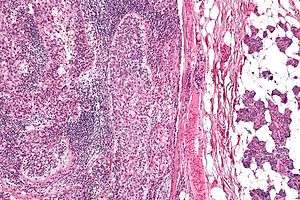

| Micrograph of a sebaceous carcinoma (left of image) metastatic to the parotid gland (right of image). H&E stain. | |

Well-differentiated and moderately differentiated sebaceous carcinoma tend to exhibit vacuolization within the cytoplasm of the tumor cells.[7] Histology may mimic basal cell carcinoma.